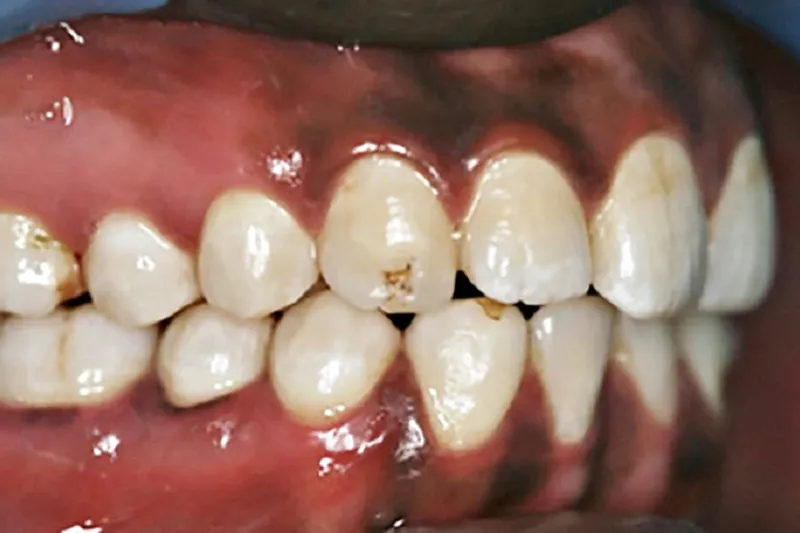

Denne artikel fokuserer på et spørgsmål, som i sagens natur først for relativt nylig er blevet aktuelt i de nordiske lande, nemlig om en øget etnisk mangfoldighed i befolkningen også afspejles i den orale sundhedstilstand og i ændrede manifestationer af orale sygdomme.

Vi præsenterer nogle af de tilgængelige videnskabelige svar på disse meget relevante spørgsmål, fx de genetiske og sociale faktorer, som påvirker caries og parodontitis.

Vi reflekterer også over, at tandplejepersonale i Norden kan have behov for at være forberedt på, at indvandrere med en anderledes baggrund også kan have anderledes behandlingsbehov.

I de nordiske lande er populationen i dag etnisk blandet, og dette indebærer, at tandplejen må tilpasse sig til den ændrede virkelighed. Ud fra sin etniske og kulturelle baggrund kan patienten have specifikke ønsker med hensyn til tændernes form og farve, andre holdninger til kost og mundhygiejne samt andre madvaner, end vi inden for tandplejen er vant til. Dagens tandpleje kan derfor ikke pr. automatik regne med, at bestemte behandlinger eller ønsker er passende, men må også forholde sig til kulturelle aspekter i forbindelse med behandlingsplanlægningen.